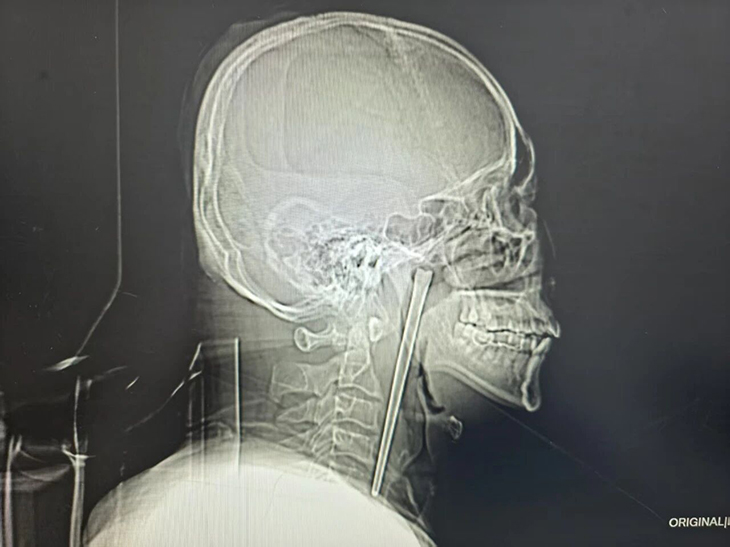

Ông Wang, 46 tuổi, gần đây đến Bệnh viện Trung tâm thành phố Đại Liên, tỉnh Liêu Ninh vì đau họng dữ dội kèm cảm giác có dị vật. Kết quả chụp X-quang khiến các bác sĩ bất ngờ: một vật thể dài khoảng 12 cm nằm trong cổ họng bệnh nhân. Khi được hỏi, ông Wang thản nhiên cho biết đó là chiếc đũa kim loại mà ông vô tình nuốt phải từ 8 năm trước.

Ảnh chụp X-quang chiếc đũa dài khoảng 12 cm nằm trong cổ họng bệnh nhân. Ảnh: O.C